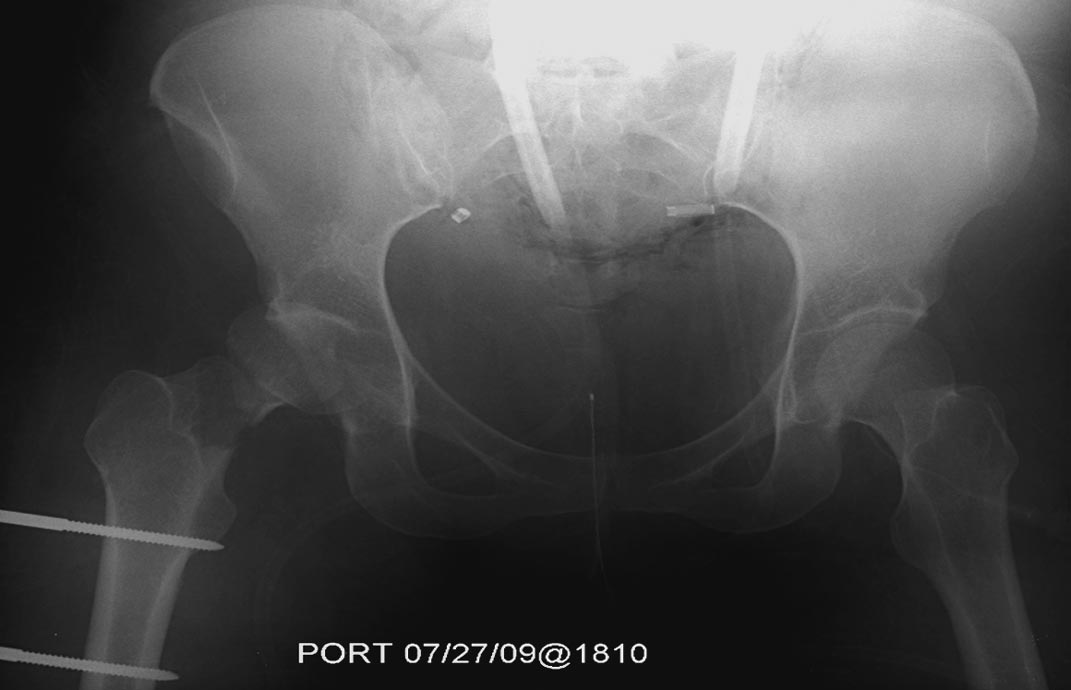

Травма хирург принял решение продолжать лечение в операционной. Срочная диагностическая лапаротомия с абдоминальной тампонадой, переливание 5 единиц крови. Irrigation & Debridement открытых ран с вакуумированием, попытка закрытой репозиции деформации сустава. По-прежнему состояние тяжелое, но давление стало стабилизироваться. Смогли получить первые диагностические данные.

Здесь перечислены ортопедические повреждения: Rt. femoral shaft fracture, Rt femoral head fracture-dislocation, Rt distal femur fracture, Rt. open patella fracture, Rt. talus fracture dislocation, Rt. open humerus fracture, Left 5th metatarsal fracture, Left dislocation 1st TMT.

Интенсивные реанимационные мероприятия продолжаются в ICU, на следующий день сделана Irrigation &Debridement раны живота с последующим ушиванием серозной оболочки, наружный фиксатор на правое бедро. В связи со стабилизацией состояния получили добро на короткую операцию. Каккое из повреждении является более приоритетным? С чего начать?

На 25 день с момента травмы операция на Jackson table с боковым обширным доступом. Удаление стержней с местной обработкой. В тазобедренном суставе удаление головки, на дне вертлужной впадины полная отслойка хряща. Вертлужный компонент с одним винтом и короткая ножка - Fitmore press fit stem. На второй день однократно доза радиации для профилактики гетеретопической оссификации. Послеоперационный период без температуры. Выписана. Нагрузку разрешили на левой стороне, а полная в 3 мес. Здесь снимки при амбулаторном наблюдении: послеоперационно, 2 мес, 3 мес и 6 мес. Нагрузка полная, отсутствует хромота, и нет жалоб.